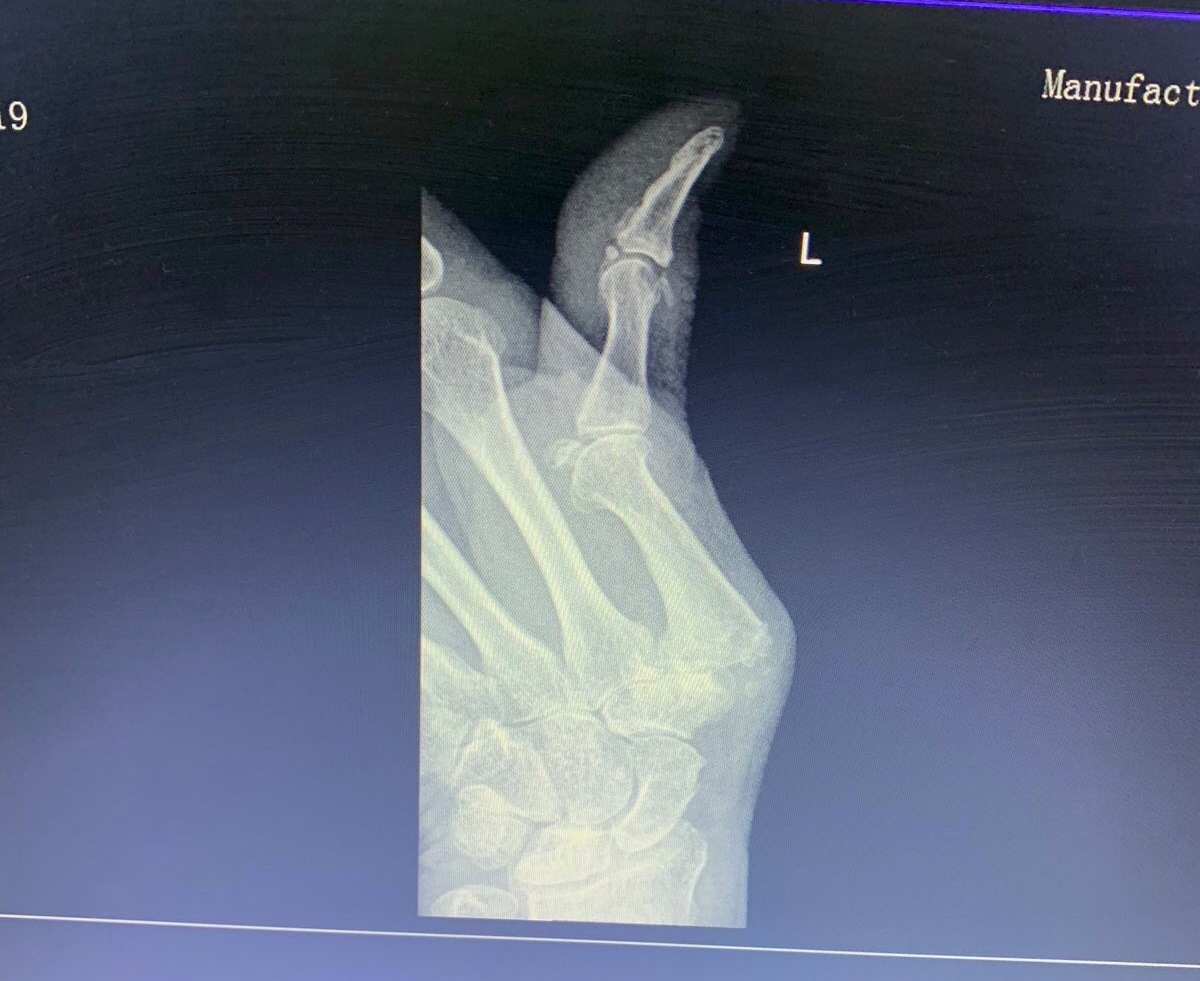

Oddelenie úrazovej chirurgie Fakultnej nemocnice s poliklinikou Žilina naďalej rozvíja a zvyšuje kvalitu poskytovanej zdravotnej starostlivosti zavádzaním nových typov operácií pre pacientov. Tím žilinskej traumatológie opätovne rozšíril portfólio výkonov a po prvýkrát úspešne zrealizoval implantáciu umelej náhrady 1. karpometakarpálneho (koreňového) kĺbu palca. Operačný výkon vykonáva na Slovensku len niekoľko špecializovaných pracovísk.